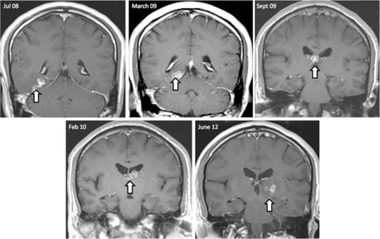

英国で初めて報告例があった、脳内に寄生した条虫の動きを示した脳スキャン画像(2014年11月20日提供、資料写真)。

(c)AFP/GENOME BILOGY/NAGUI ANTOUN